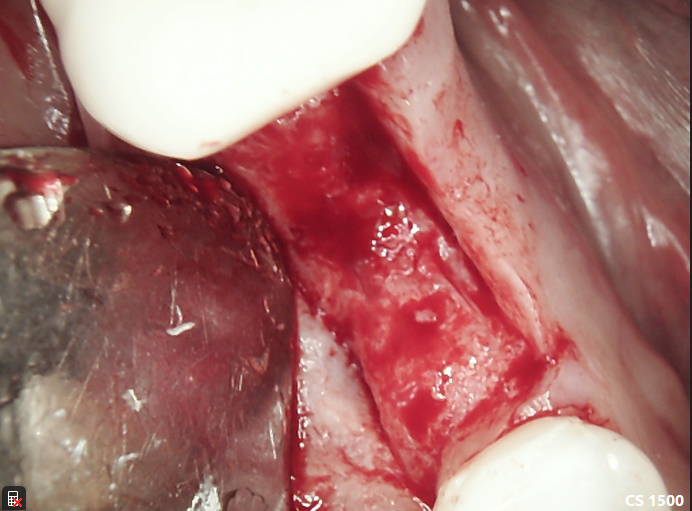

This is a case we started earlier in the year. Digital Scanning for impression-all modeless. The contacts were perfect. Slight occlusal adjustment. Thin ridge originally, bone graft slide missing. PTFE for sutures, the doctor prefers PGCL because it does not stretch as much. Note the buccal profile after restoration and the mesiodistal gentle S-Curve of the abutment. Look for the stability of crestal bone levels and the increase in bucco-lingual width along with a wide thick band of keratinized tissues. This patient was seen 4 times. Once for the initial surgery (1 hr), post op ck (15 min) impression (30 min), and final checking process (30 min – could’ve been 15). Contacts were perfect-no adjustments were needed.